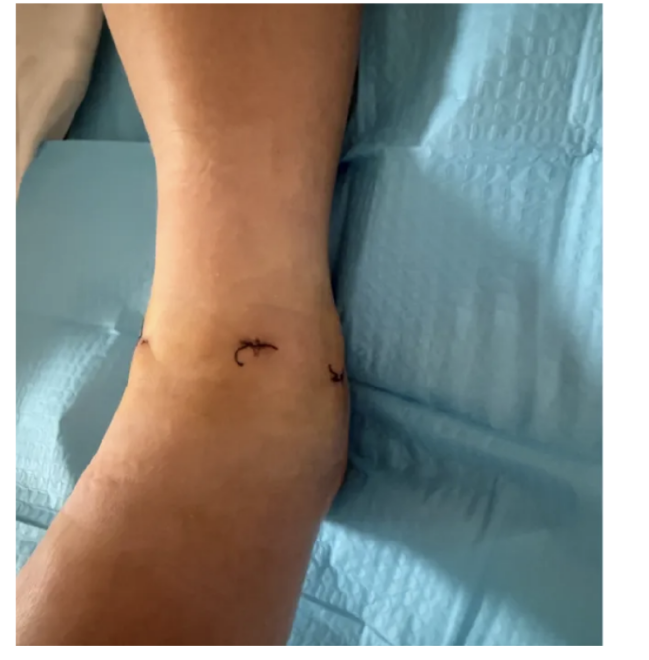

三个3mm的微小切口,大大减少了对患者踝关节周围软组织的损伤,术中出血量极少,术后疤痕隐蔽,既保证了治疗效果,又兼顾了美观需求。

手术切口仅为3个3mm小切口